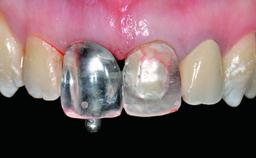

Replacement of a Compromised Upper Right Central Incisor: Hard- and Soft-tissue Augmentation, Late Placement of an RC Bone Level Implant

A 36-year-old male patient with a compromised maxillary central incisor was referred by his general dentist for consultation. The patient’s chief complaints were the gradual debonding of a temporary crown on the right central incisor and unsatisfactory esthetics due to an increasing diastema between the right central and lateral incisors. The patient reported a traumatic event some years previously, when a crown had been placed after root-canal treatment. The referring dentist wanted to provide a new crown restoration, but was concerned about the condition of the residual root. Anamnesis was negative for any other dental or periodontal pathology in the remaining dentition. The patient reported taking no medications: He was a smoker (10 to 15 cigs/day) and had realistic esthetic expectations.